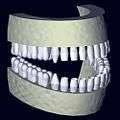

As a 3D rendition, CBCT offers an undistorted view of the dentition that can be used to accurately visualize both erupted and non-erupted teeth, tooth root orientation and anomalous structures that conventional 2D radiography cannot.[9]

Processing example using x-ray data from a tooth model: